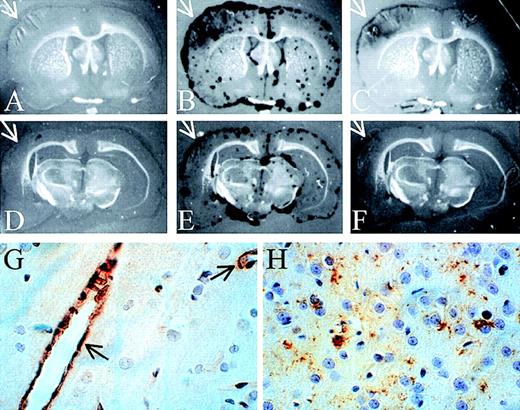

To examine the distribution of proteinase activity within the brains of the PBS- and neuroserpin-treated animals, in situ zymography of frozen brain sections was performed. These data demonstrate that, like the SDS-PAGE zymography, all of the proteolytic activity detected in both control and neuroserpin-treated brains was plasminogen dependent, because no proteinase activity was observed in the absence of plasminogen (Figure 5A,D). At 6 hours after reperfusion, proteinase activity in all sections was primarily associated with the meningeal tissues of both ipsilateral and contralateral sides. This activity was also completely blocked by the addition of anti-tPA antibodies, indicating that the majority of PA activity within the brain at this time is tPA (data not shown). In contrast, by 72 hours after reperfusion, there was a large increase in plasminogen-dependent proteolytic activity ipsilateral to the stroke in control animals (Figure 5B), and unlike the sections at 6 hours or the 72 hours contralateral side, this activity was not restricted to the meninges and was not completely blocked by the addition of anti-tPA antibodies to the plasminogen overlay (arrows in Figure 5B,C). In neuroserpin-treated animals this zone of proteinase activity was significantly smaller than in the untreated animals (Figure 5E,F). This suggests that by 72 hours much of the plasminogen-dependent activity within the region of the stroke was not tPA. Consistent with this, the addition of anti-uPA antibodies to the plasminogen overlay markedly reduced proteolysis within the area of the stroke while having no effect on the proteolytic activity in the meningeal tissues contralateral to the stroke (data not shown). This implies that within the area of the infarct at 72 hours following reperfusion there is a significant increase in uPA activity. These results also suggest that there is not a large up-regulation of either tPA or uPA immediately following stroke; however, by 72 hours after reperfusion, uPA-catalyzed proteolysis is significantly increased specifically within the region of the infarct. These results are also consistent with the SDS-PAGE zymography and suggest that the lesser increase in uPA activity observed by SDS-PAGE zymography in neuroserpin-treated animals may simply reflect the smaller size of the infarct in this group and not a direct inhibition of the up-regulation of uPA-activity by neuroserpin.

In situ zymography and immunohistochemical staining of brain sections

. In situ zymography in panels A-F; panels A and D are developed without plasminogen, and all other panels are developed with plasminogen. Panels C and F also contain anti-tPA antibodies. The white arrows indicate the area of the infarct (magnification × 3). (G) Immunohistochemical staining of tPA 6 hours after reperfusion. The black arrows indicate tPA-positive blood vessels. (H) Immunohistochemical staining of uPA in the area of penumbra 72 hours after reperfusion (magnification in G and H × 400).

Immunohistochemical staining for tPA indicated that by 6 hours after reperfusion, tPA antigen was detected only within the vascular endothelial cells and not within neuronal cells (Figure 5G). Consistent with the relatively low levels of uPA activity at 6 hours, no uPA staining could be detected in these sections (data not shown). However, by 72 hours after reperfusion, uPA immunoreactivity was readily detected, but only in the area of ischemic penumbra (Figure 5H). This is consistent with the in situ zymography analysis demonstrating uPA activity predominantly within the cortex and only at 72 hours after reperfusion. Finally, at 72 hours in neuroserpin-treated animals, there was a marked reduction in the overall area where uPA antigen was detected but not in the intensity of the staining, compared to PBS-treated animals (data not shown). This further suggests that the reduced uPA activity observed by zymography was likely due to the reduced size of the infarct in neuroserpin-treated animals.